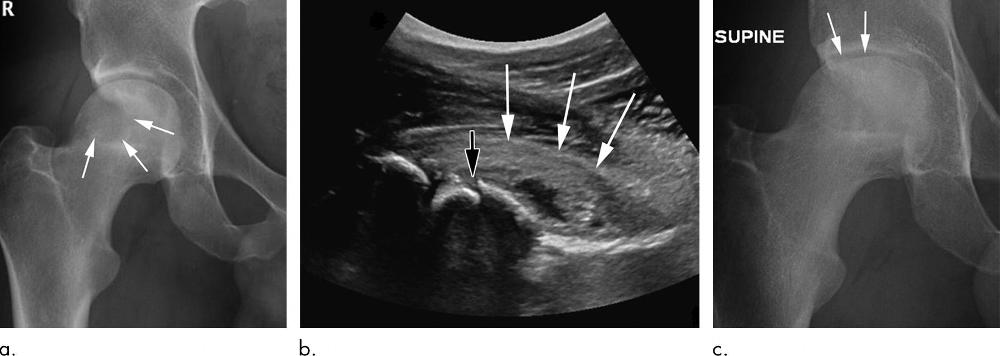

Figure 1. Rapid progressive osteoarthritis joint space loss (type 1) in a 61-year-old woman who presented with hip pain. (a) Anteroposterior left hip radiograph shows joint space narrowing (arrowheads) and femoral and acetabular osteophytic changes (arrows) consistent with Kellgren-Lawrence grade III hip osteoarthritis. She was referred for US-guided steroid injection. (b) Four months after intraarticular corticosteroid injection, she presented with worsening left hip pain. Anteroposterior hip radiograph shows severe interval joint space narrowing (arrowheads) and enlarging subchondral cysts (arrows). (c) Coronal intermediate-weighted fat-suppressed MRI obtained at the same time as b shows complete loss of the acetabular and femoral cartilage (arrowheads), with subchondral cystic changes (black arrows). In addition, there is joint effusion and synovitis (*) and periarticular soft-tissue edema (white arrows). This patient underwent total joint replacement 3 months later.